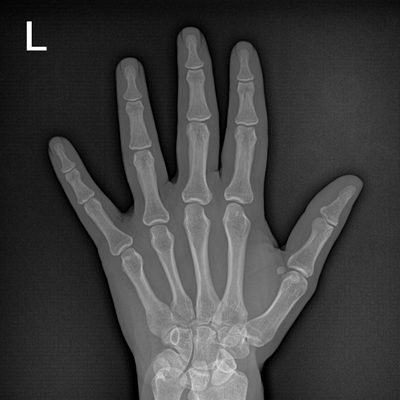

輕量化設(shè)計(jì) 小巧靈活 PLX5100

用于影像科、急診室、病房、ICU、手術(shù)室等多場景應(yīng)用。

● 數(shù)字化無線平板成像,操作簡便,成像質(zhì)量高

● 配備移動筆記本,無線圖像采集,無線PACS傳輸